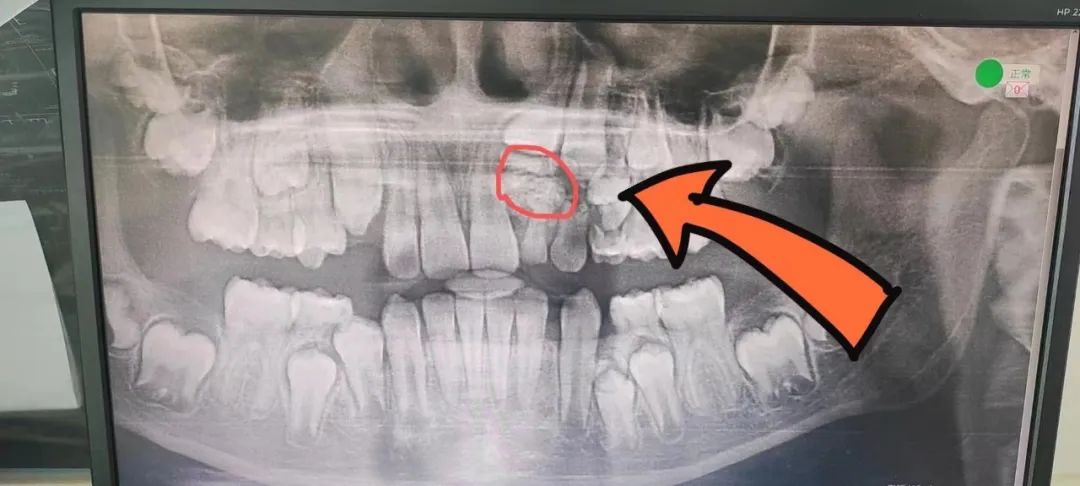

▲口腔全景片可見:除左上區(qū)域有直徑10㎜的牙瘤外,左下方前磨牙區(qū)也存在較小范圍的牙瘤。

近日,細(xì)心的李女士(化名)覺得孩子妞妞(化名)乳牙長時(shí)間滯留、恒牙長時(shí)間未萌出,于是帶其到北大醫(yī)療淄博醫(yī)院口腔科就診??谇豢浦魅蚊两釉\了妞妞,在進(jìn)行全景片檢查時(shí),毛主任發(fā)現(xiàn)其左側(cè)上頜骨中,竟然有一個(gè)巨大的球狀“白影”,有多枚沒發(fā)育完全的牙齒,像巖石一樣阻礙了新生門牙的生長,這些沒有發(fā)育完全的牙齒,正是導(dǎo)致妞妞她沒有萌出恒牙的“罪魁禍?zhǔn)?,而這正是“牙瘤“?!把懒觥毙枰中g(shù)切除,才能恢復(fù)牙齒健康,讓正常的牙齒健康生長,毛主任耐心對(duì)李女士講解后,李女士迫切希望盡快手術(shù)治療。?

毛亮主任與口腔科專家為其制定了詳細(xì)手術(shù)方案,在手術(shù)室醫(yī)護(hù)人員的密切的配合下,毛主任利用無痛麻醉技術(shù)進(jìn)行精準(zhǔn)麻醉,拔除對(duì)應(yīng)部位乳牙,去除牙瘤表面的骨質(zhì),打開一個(gè)微小開口,取出了左上區(qū)直徑約1.1厘米及左下區(qū)直徑約0.6厘米的“牙瘤”,手術(shù)僅耗時(shí)30余分鐘。經(jīng)毛主任清點(diǎn),牙瘤中竟有約30多顆大小不同、形狀各異阻礙新生牙齒生長的小牙齒。